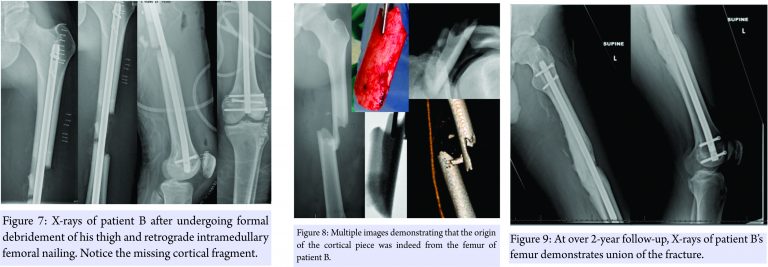

Patient B was then taken to the operating room for an irrigation and debridement of his left thigh and retrograde intramedullay nailing of his femur. The patella and femoral condyle fractures did not meet operative criteria. A long discussion was had with the patient and his family about how to best treat the bone loss from the femur. Due to the possibility of disease transmission, infection, and the fact that it was not involving the articular surface, the free piece of cortical bone was discarded. Since the patient was a young, healthy male with 50% apposition of intact femur, we decided to proceed with operative fixation of the femur without graft augmentation. A locked, retrograde femoral nail was used to stabilize the fracture (Fig. 7). Fig. 8 shows a side by side comparison of the extruded bone. He was made weight bearing as tolerated and was discharged home on post-operative day number 3.

At over 2-year follow-up, patient B had union of his fracture with no negative sequelae (Fig. 9). He was able to return to his profession full-time, as an electrician.